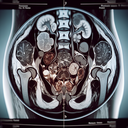

МРТ нирок

МРТ нирок — це неінвазивне дослідження, яке дозволяє отримати детальні зображення нирок та прилеглих структур. Метод використовує магнітне поле та радіохвилі для створення якісних зображень. ### Основні показання до МРТ нирок: - Підозра на пухлини або кісти...

МРТ наднирників

Магнітно-резонансна томографія (МРТ) наднирників – це неінвазивне обстеження, яке дозволяє отримати детальні зображення цих залоз, що розташовані над нирками. **Переваги МРТ наднирників:** 1. **Безпека**: Використовуються магнітні поля та радіохвилі, без іонізуючого випромінювання...